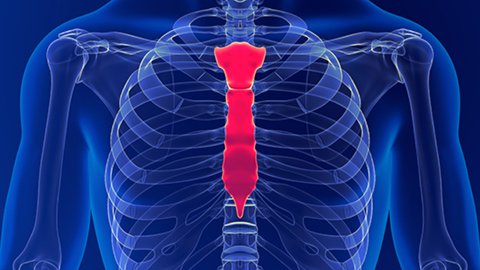

A client who was recently in a motor vehicle accident was “cleared for massage” by her primary care provider. But it turns out she had no X-rays and that hid the fact that she sustained a fracture to her sternum. What is the responsibility of the massage therapist when a client has been “cleared for massage”? Ruth has some thoughts.